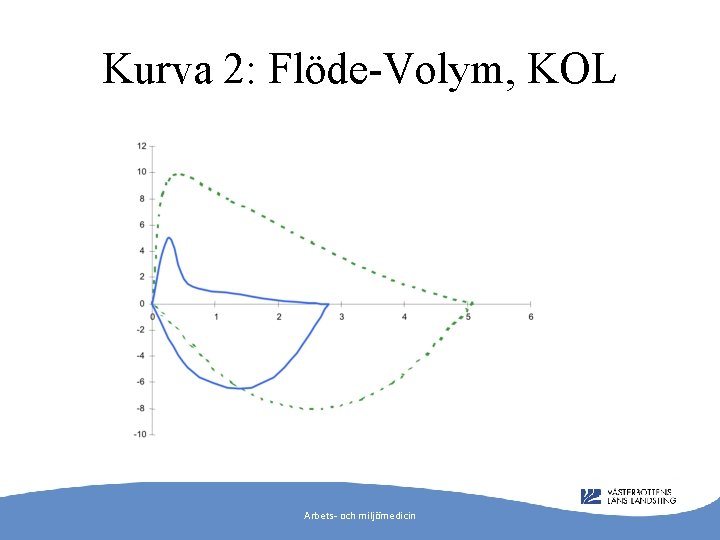

Kurva 2: Flöde-Volym, KOL Arbets- och miljömedicin